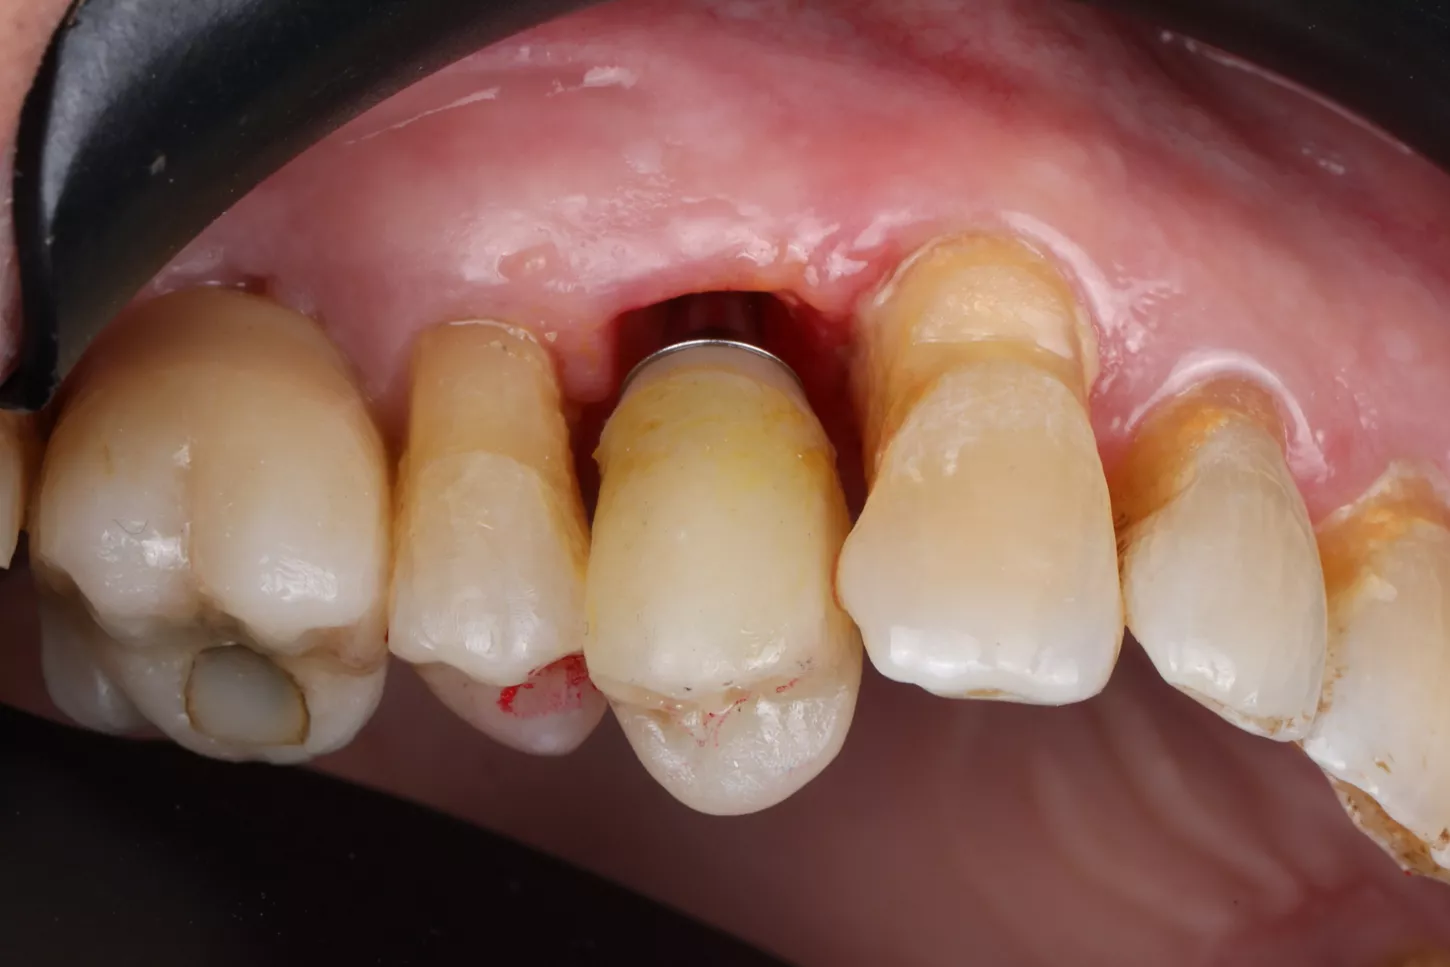

After healing, implant placement was performed using a tooth-supported surgical guide under local anaesthesia. A limited buccal flap allowed visual control and creation of a pouch for a connective tissue graft. Osteotomy was completed with the Integral surgery kit, and a 3.4×12 mm Axiom® X3 implant (XT34120) was placed under fully guided conditions with a Healfit® SH (OPSHSC23) healing abutment connected. A palatal connective tissue graft was positioned buccally to enhance soft-tissue thickness. The flap was sutured with 5-0 interrupted and mattress sutures. Postoperative care mirrored Phase I, with uneventful healing observed (Fig 4 a&b).

4a. 4b. Lateral view showing Healfit® SH healing screw connected to the implant and occlusal view of sutures for tension-free closure.